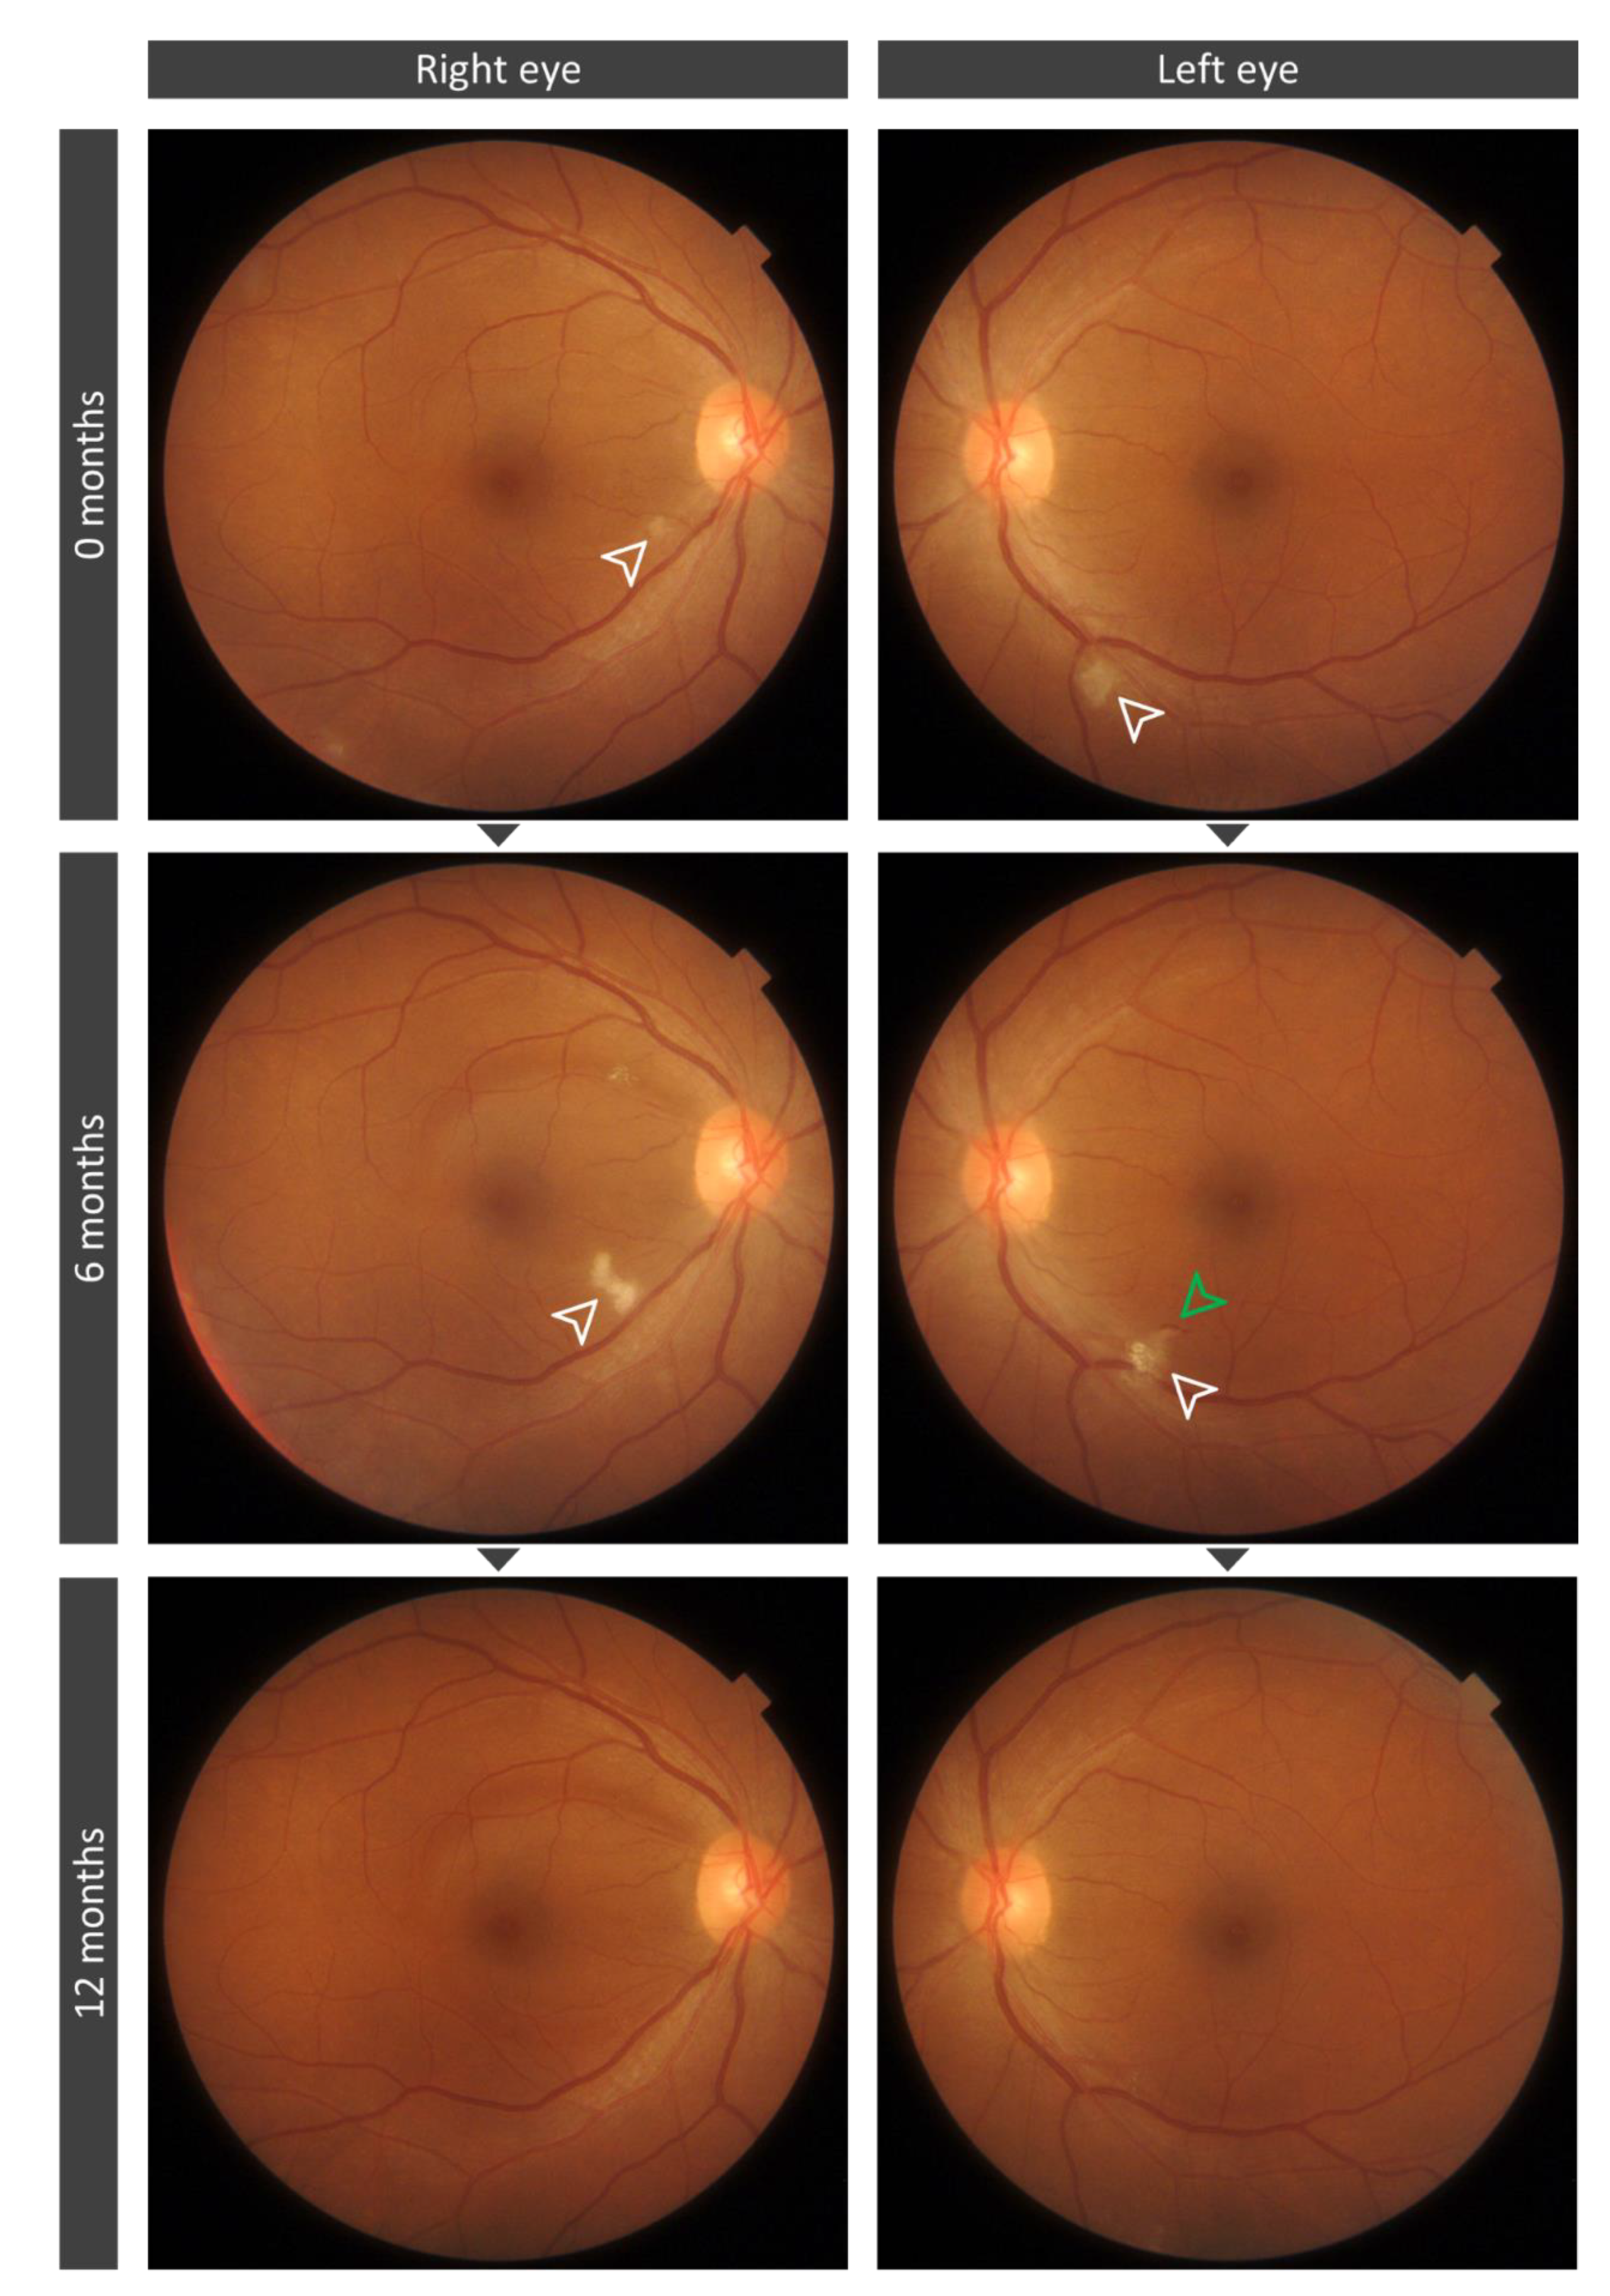

3.4. Cotton Wool Spots Analysis